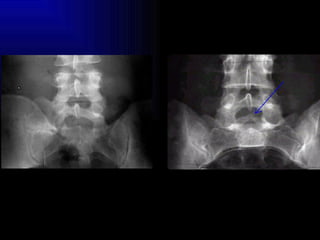

Espondilolisis Pars interaricularis Espondilolistesis GI, GII, GIII

El “perrito”

Espondilolisis